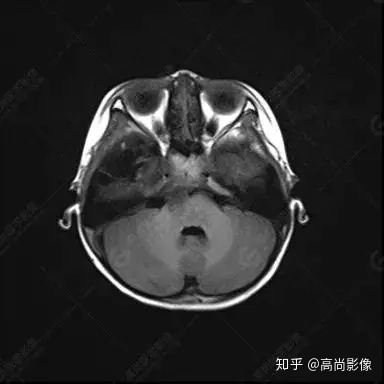

右側(cè)顳葉腫瘤切除術(shù)后(具體不詳):右側(cè)顳部骨質(zhì)不連續(xù)呈術(shù)后改變,右側(cè)顳葉術(shù)區(qū)見片狀長T1長T2信號(hào)影,F(xiàn)LAIR呈低信號(hào);術(shù)區(qū)后方右側(cè)顳枕葉見一巨大占位性病變影,邊界欠清,大小約6.2×5.8×4.3cm(前后×左右×上下),信號(hào)不均勻,T1WI呈等稍低信號(hào)間雜少許高信號(hào),T2WI呈高稍低混雜信號(hào),DWI示部分病灶彌散受限,相應(yīng)ADC圖減低,磁敏感序列見部分呈極低信號(hào),增強(qiáng)掃描可見明顯不均勻強(qiáng)化,鄰近硬腦膜及小腦幕增厚并明顯強(qiáng)化;另延髓右前方及右側(cè)橋小腦角區(qū)見一不規(guī)則形異常信號(hào)影,大小約3.2×1.3×3.7cm(左右×前后×上下),呈長T1稍長T2信號(hào),F(xiàn)LAIR呈等信號(hào),DWI未見受限,增強(qiáng)后明顯均勻強(qiáng)化,鄰近腦膜明顯強(qiáng)化。鄰近腦實(shí)質(zhì)及右側(cè)顳角明顯受壓;左側(cè)大腦半球未見局灶性信號(hào)異常,中線結(jié)構(gòu)稍左移。

右側(cè)顳葉腫瘤切除術(shù)后:現(xiàn)術(shù)區(qū)后方右側(cè)顳枕葉及延髓右前方占位,右側(cè)顳枕部硬腦膜及小腦幕明顯強(qiáng)化,結(jié)合既往影像資料,考慮為胚胎源性惡性腫瘤,如非典型畸胎樣/橫紋肌樣瘤(AT/RT)或原始神經(jīng)外胚層腫瘤(PNET)。